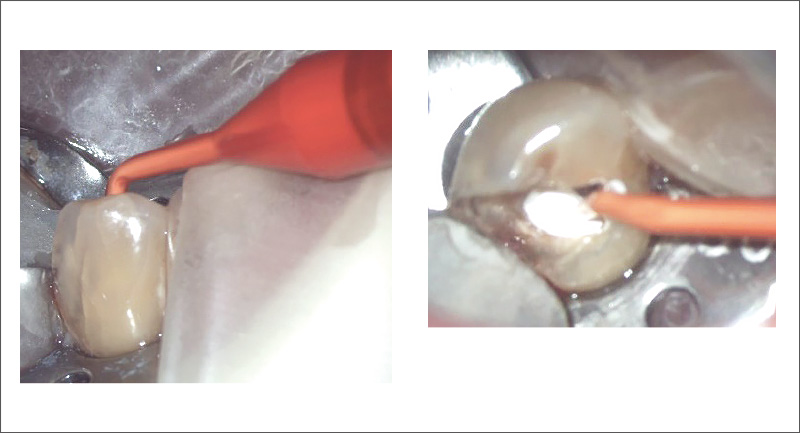

![[写真] 水が残る分岐した根管への根管充填](/academic/dentalmagazine/wp-content/uploads/sites/2/2025/09/194-1_photo06.jpg)

図6 水が残る分岐した根管への根管充填

ノズル先端(橙矢印)からシーラーを押し出すのみで、分岐した両根管の根尖孔から根管上部まで充填された(白矢印)。 -

![[写真] 管間側枝への根管充填](/academic/dentalmagazine/wp-content/uploads/sites/2/2025/09/194-1_photo07.jpg)

図7 管間側枝への根管充填

ノズル先端(橙矢印)から押し出されたシーラーは管間側枝(黄矢印)を通り、もう一方の根管も過不足なく充填された。 -